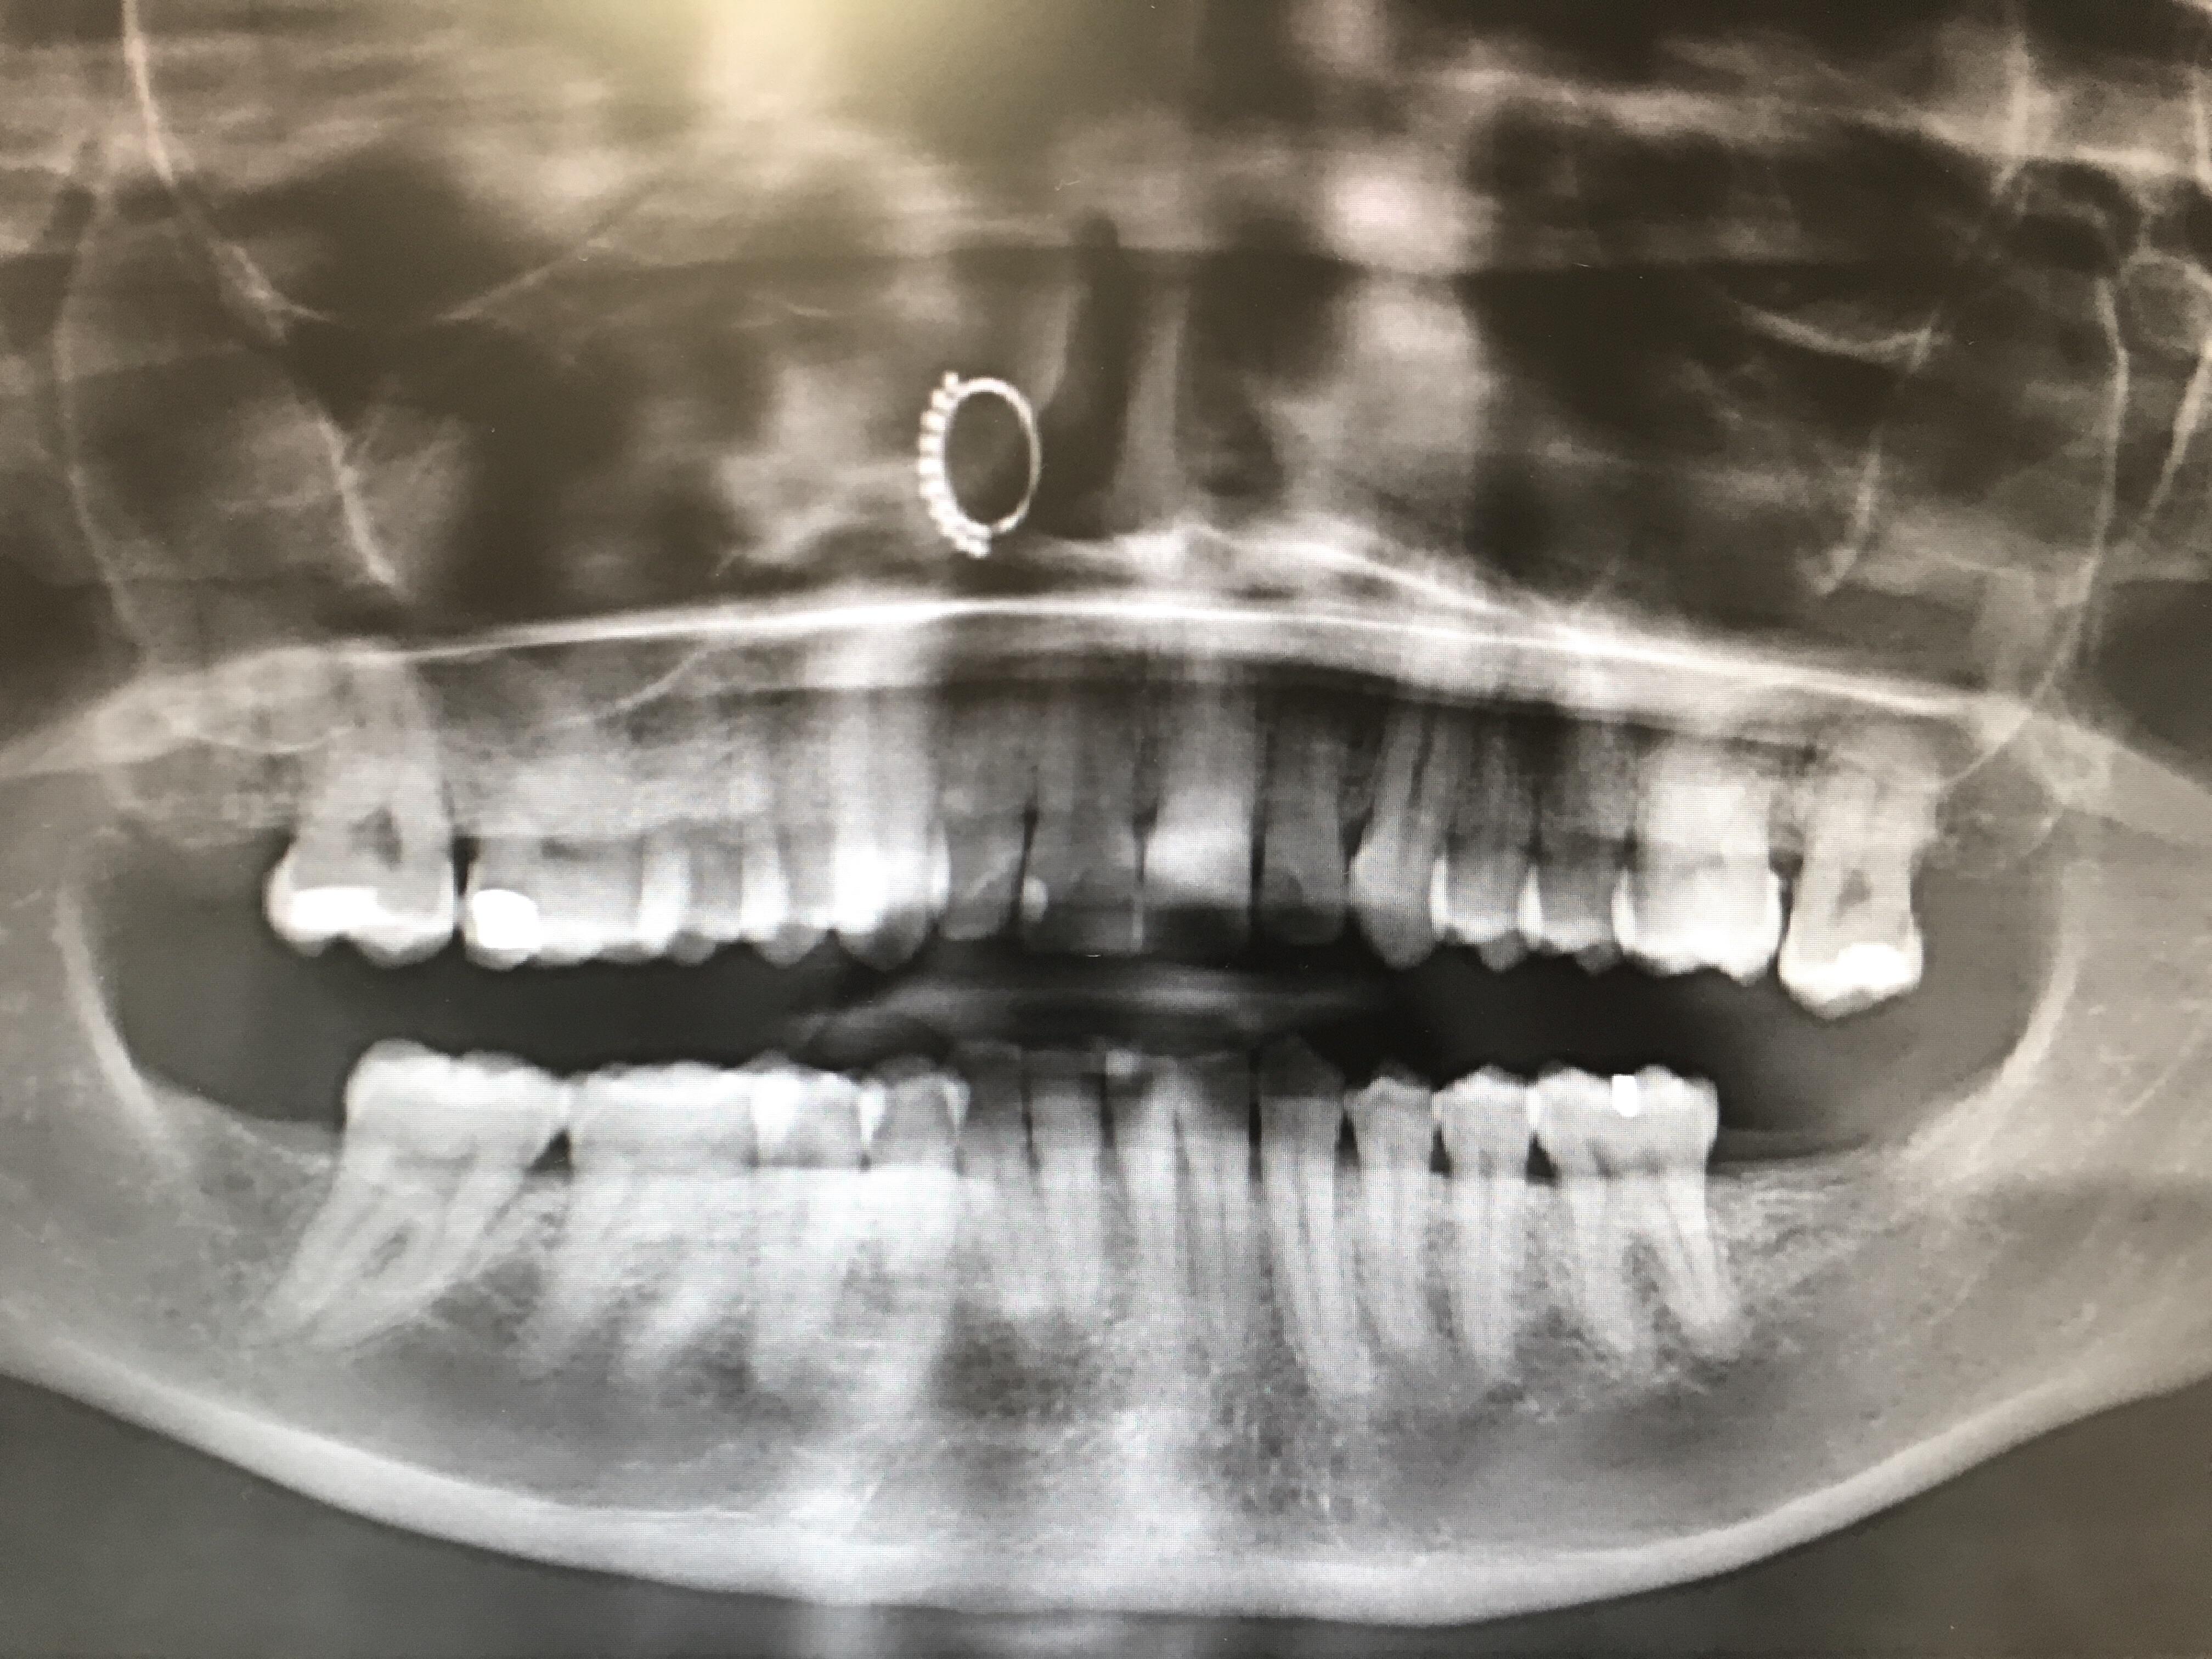

You can see my nose ring in my dental xray. r/mildlyinteresting Nose Ring Dental X Ray For intra oral ones then they can be left in. As for record keeping, a dentist may. However its up to the clinician to. Contact us for costs and all types of x. For extra oral they ideally should be taken out but. The nose ring will appear on the xray in an area that can block a possible tooth. Nose Ring Dental X Ray.

got my first xray with all my piercings in taken at the orthodontist Nose Ring Dental X Ray However its up to the clinician to. As for record keeping, a dentist may. Contact us for costs and all types of x. For extra oral they ideally should be taken out but. For intra oral ones then they can be left in. The nose ring will appear on the xray in an area that can block a possible tooth. Nose Ring Dental X Ray.